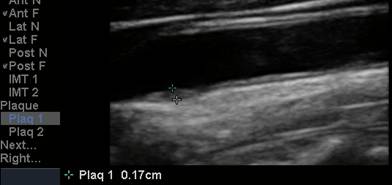

The CIMT procedure is

simple. An ultrasound study is carried out of the carotid arteries in your

neck. A specialized software program is used to precisely measure the mean and

maximum IMT. Standard carotid ultrasound is looking for “flow-limiting”

stenoses, narrowings that could be addressed surgically. This is not what we

are interested in with CIMT testing - we will be measuring soft plaque

accumulation in non-overtly diseased vessel segments (if plaque is identified we

measure the CIMT at an adjacent, normal appearing segment). While the presence

of plaque obviously has significance, it is the IMT parameter that best predicts

the presence and severity of atherosclerotic vascular disease elsewhere in your

body, it’s risk of progression, and your risk of sustaining an atherosclerotic

event (think of IMT as the “staging ground” for obstructive plaque – the higher

the IMT, the greater the rate of IMT progression, the more rapidly will large,

obstructive plaques form). Over 2,000 studies (go to www.pubmed.gov and enter

Carotid IMT) document the link between CIMT and current risk, and an even more

powerful relationship between the rate of change in CIMT and future risk. We

will use CIMT to help us decide who should be treated with preventive measures

and how aggressive our efforts should be. We will use the rate of change of

CIMT to gauge the success of the regimens that we construct for you.

We have already found undiagnosed, “surgical” narrowings during IMT testing of “normal” individuals. If potentially obstructive plaque is identified, we will refer you for a formal carotid ultrasound, which involves blood flow velocity measurement to quantify the degree of vessel stenosis.